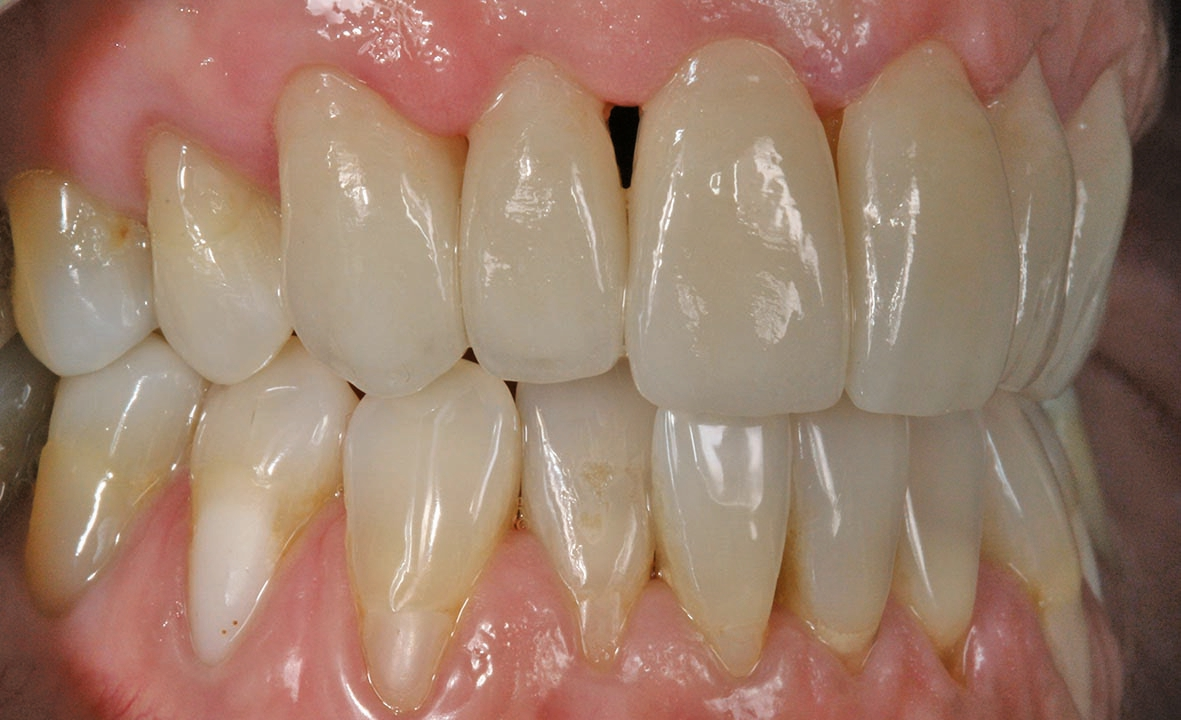

Unsere Patientin stellte sich mit einer starken Parodontitis (Abb. 1a–c) und einer schlechten Mundhygiene in der Praxis von Zahnarzt Andreas Klinkisch (Weidenberg und Bischofsgrün) vor. Am Anfang standen zunächst die Motivation zur besseren Mundhygiene, dann die konkrete Anleitung zum gründlichen Zähneputzen und schließlich die Begleitung der Maßnahmen. Nach diesem Prozess, der fast ein Jahr beanspruchte, stellte sich die 67 Jahre alte Patientin bei mir mit dem großen Wunsch vor, wieder natürliche, ästhetische und etwas hellere Frontzähne mit geschlossenen interdentalen Bereichen zu haben.

Wir sehen uns in derart gelagerten Fällen stets mit mehreren Herausforderungen konfrontiert, vor allem mit diesen: Zum einen müssen die Materialien zuverlässig und robust sein, zum anderen sollen mir die Materialien erlauben, feinste altersspezifische und individuelle Merkmale zu berücksichtigen und „nachzubauen“. Bei dieser Patientin waren die Zähne leicht fluoreszierend, das inzisale Drittel transparent und in der Schneidekante leicht opaleszent. Das Dentin und der Zahnhalsbereich hingegen wirkten stark chromatisch. Auch wollten wir, dass sich das Zahnfleisch bestmöglich an das Material adaptiert. Auch das würde helfen, die schwarzen Dreiecke im Frontbereich zu schließen.